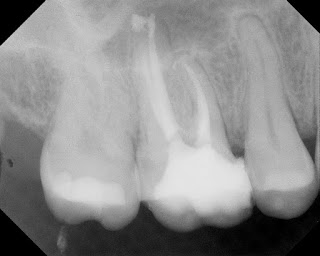

RCT was completed and returned to GP for coronal coverage.

5 year recall of the tooth finds it fully functional and asymptomatic. Note the fine margins of the crown which play a key role in the success of this treatment. Some patients will elect to retain a natural tooth with a crack, understanding the guarded long term prognosis, rather than extract and replace it.